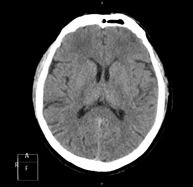

- Neuroradiology

- Skull CT

Radiological test that provides high definition anatomical images of the skull (brain stem, cerebellum, cerebrum, cranial calotte, etc.) using CT (Computed Tomography) equipment. Indicated for: trauma, headache, memory disorders, sudden loss of strength in a limb or half of the body.